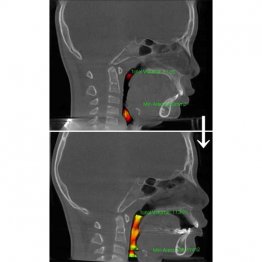

全身の健康は歯並びで分かる いびき、睡眠時無呼吸…それ「あごの位置」に問題ありかも?

歯並びの悪さやあごの骨のゆがみは見た目の問題だけではない。いびきや睡眠時無呼吸症候群、姿勢の悪化から、子どもの発達にまで影響を及ぼす可能性があるという。東京・港区の「こどもと女性の歯科クリニック」で、歯科医師の岡井有子院長に話を聞いた。